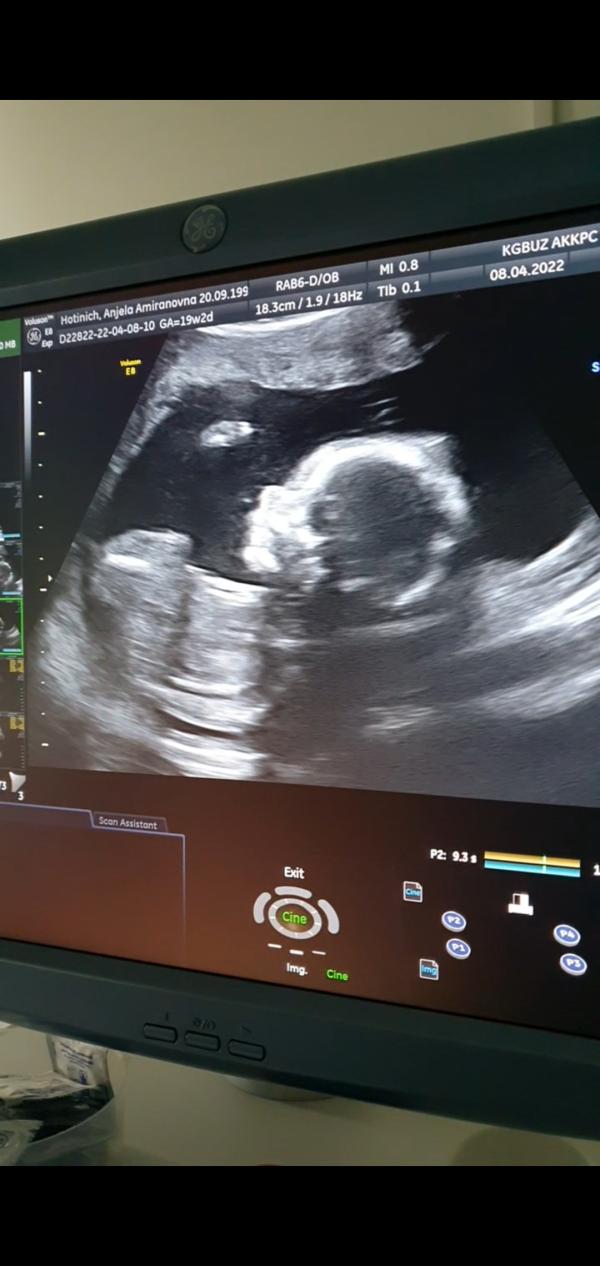

ВТОРОЙ СКРИНИНГ💞

Я так жду УЗИ, чтобы вновь увидеть малыша и узнать, все ли у него в порядке🤗

По прежнему, с первого раза остался гиперэхогенный фокус в левом желудочке сердца, и немного большовато овальное окно.

Ну сказали явных пороков нет...фух! это лишь небольшие изменения, которые к моменту рождения должны прийти в норму🙏